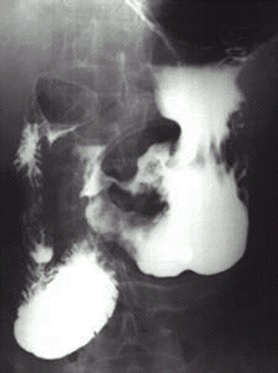

04卷-5.病史:男性,62岁,上腹不适,恶心、呕吐5个月,大便潜血阳性3周。诊断

A.十二指肠球溃疡

B.胃溃疡

C.胃癌

D.胃炎

【该题针对“ X线-消化道穿孔 ”知识点进行考核】